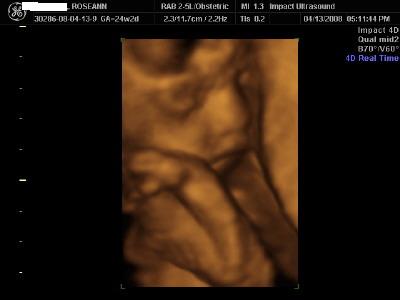

I just did the gold this past weekend and loved it

With tax, etc and the coupon, it came to 165 for the gold package.

I got a comfy bed and all the parents sat on couches and the sono was put up on a movie screen so everyone could see. My baby kept flipping but we were able to get him to cooperate and I got good pics. We got an 8 minute video, 6 3D pics printed out, and about 15 black and white 2D pics, plus a CD with about 20 3D pics. Both our families oved it Here are 2 of my pics - I was in my 25th week Image Attachment(s):